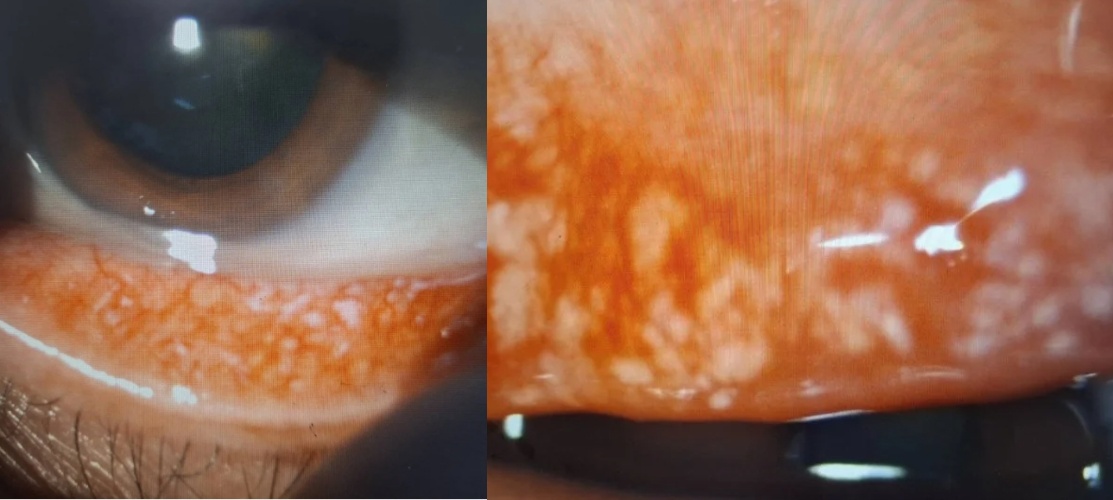

洪啟庭在檢查中發現,該名國手右眼約有600顆、左眼約400顆眼結石,總數逼近千顆,規模之大前所未見。這些結石突出結膜表面後,每次眨眼就如同「砂紙刮角膜」,造成嚴重的角膜撕裂傷,視力一度從正常值降至0.5與0.4。儘管醫療團隊已透過手術逐一清除,但由於國手無法降低用眼負荷,3個月後回診發現眼結石再次「重出江湖」,且體積更大。